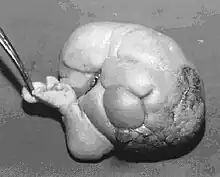

The postoperative specimen from the previous image shows a fairly well developed fetus lying on its back, with rudimentary digits.